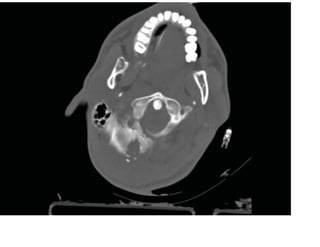

Fenêtres osseuses avec balle logée

Les images tomodensitométriques

axiales des diapositives suivantes

montrent le point d'entrée de la balle

dans le crâne occipital droit avec des

fragments de fracture comminutive.